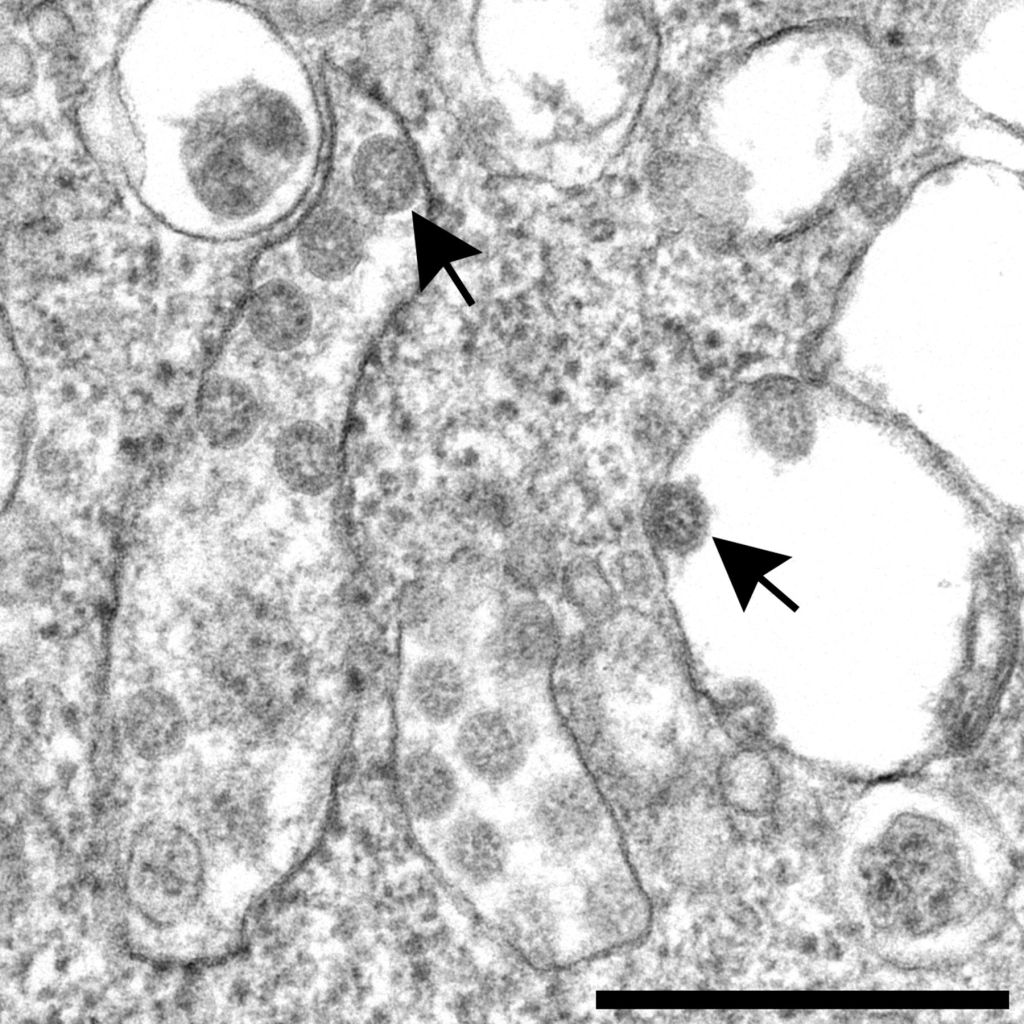

While viruses were discovered only decades after Koch, cannot be cultured in the classic sense, and cannot be seen with a conventional light microscope, they are still very real. Viruses aren’t exosomes (extracellular vesicles), either, but exosomes can play a role in virus infections and viral disease.